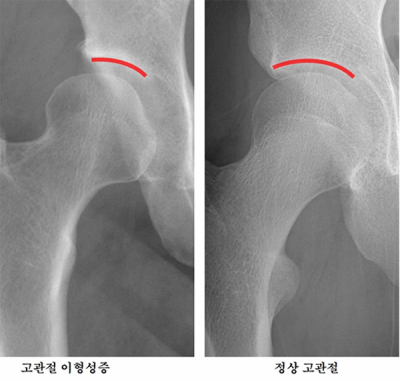

°í°üÀý ÀÌÇü¼ºÁõÀº ´ëÅð°ñµÎ¸¦ °¨½Î´Â °ñ¹Ý ÂÊ °üÀý(ºñ±¸)ÀÌ ¼±ÃµÀûÀ¸·Î ¾è°Ô Çü¼ºµÅ °í°üÀýÀÇ ¾ÈÁ¤¼ºÀÌ ¶³¾îÁö´Â ÁúȯÀÌ´Ù. Á¤»óÀûÀÎ °í°üÀýÀº °øÃ³·³ »ý±ä ´ëÅð°ñµÎ°¡ ±×¸© ¸ð¾çÀÇ ºñ±¸¿¡ ±íÀÌ µé¾î°¡ üÁßÀ» °í¸£°Ô ºÐ»ê½ÃŰÁö¸¸, ÀÌÇü¼ºÁõÀÌ ÀÖ´Â °æ¿ì °üÀýÀÌ ÃæºÐÈ÷ µ¤ÀÌÁö ¾Ê¾Æ ƯÁ¤ ºÎÀ§¿¡ ºÎ´ãÀÌ ÁýÁߵȴÙ.